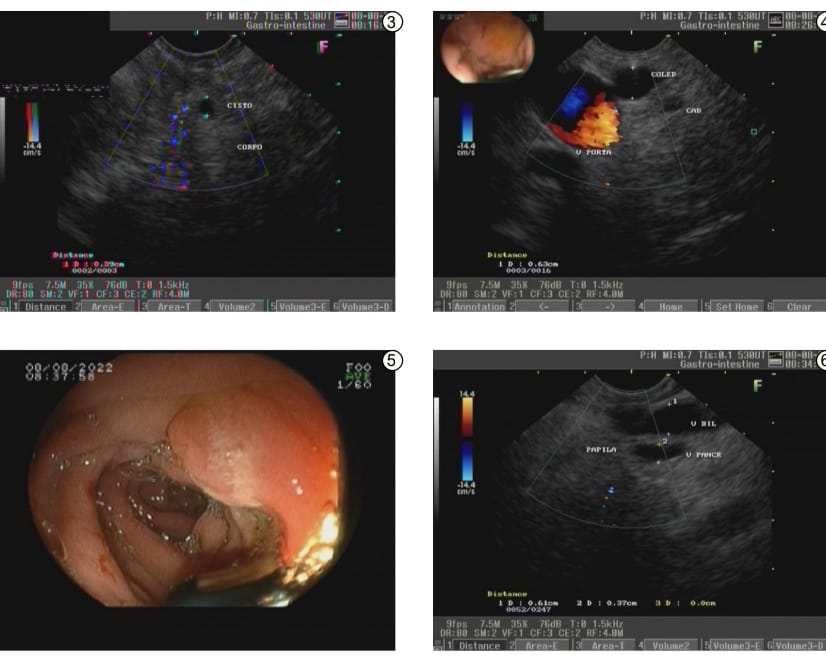

A Ecoendoscopia é uma exame de imagem que combina a tecnologia da endoscopia com a da ultrassonografia, sendo capaz de examinar a parede do trato gastrointestinal e órgãos adjacentes, como vesicula biliar, vias biliares, pâncreas, linfonodos (gânglios), vasos sanguíneos, retroperitônio, estruturas do mediastino, paredes do reto, útero.

• diagnóstico e estadiamento de tumores de esôfago, estômago, duodeno, papila duodenal, pâncreas e reto;

• avaliação de cistos, especialmente do pâncreas;

• pesquisa de microcálculos e cálculos em via biliar/vesícula biliar;